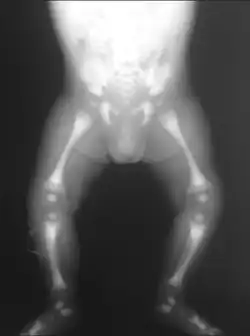

Osteopetrosis

| Adult-onset osteopetrosis (Albers-Schönberg Disease) | |

| X-ray of the pelvis of a patient with osteopetrosis, adult onset form (Albers-Schönberg disease). Note the dense appearance. | |

Osteopetrosis, literally "stone bone", also known as marble bone disease or Albers-Schönberg disease, is an extremely rare inherited disorder whereby the bones harden, becoming denser, in contrast to more prevalent conditions like osteoporosis, in which the bones become less dense and more brittle, or osteomalacia, in which the bones soften. Osteopetrosis can cause bones to dissolve and break.[1]